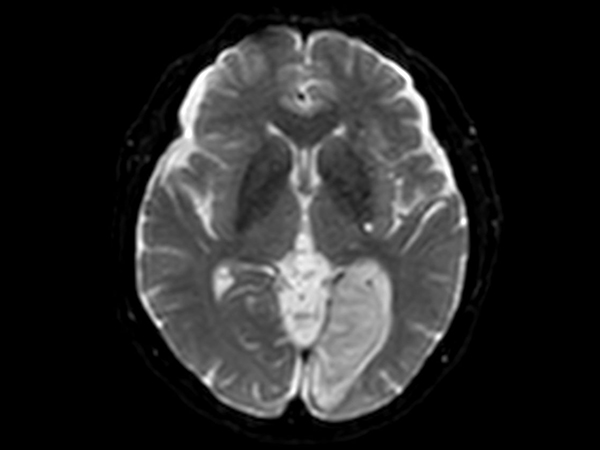

Brain infarction

Patient with a brain infarction. Compressed SENSE is used to shorten the total exam time.

Diffusion - b0

-